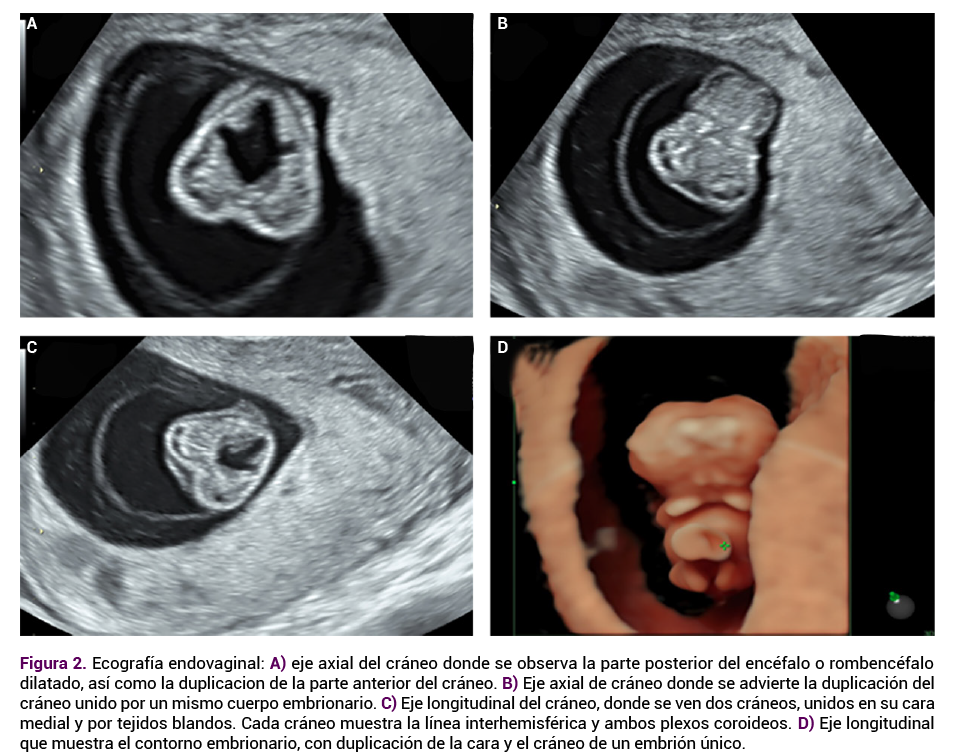

Las extremidades superiores e inferiores se apreciaron sin anormalidades aparentes. Se observó un quiste de cordón umbilical, probable onfalocele (Figura 3 A y B). Se explicó a la paciente el mal pronóstico fetal a corto plazo y la necesidad de interrumpir el embarazo. La paciente no aceptó la realización de estudio genético.

<strong>Figura 3</strong>

Figura 3. Lesión quística en cordón umbilical con sospecha de defecto de pared abdominal tipo onfalocele (vistas A y B).